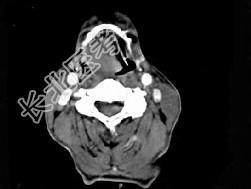

- 单项选择题男,74岁, 咽喉部不适一年余,近两三个月咽喉疼痛, 吞咽困难,CT如图所示, 最可能诊断是  (    )

- A、喉癌

- B、会厌癌

- C、声带癌

- D、声门下区癌

- E、跨声门型癌